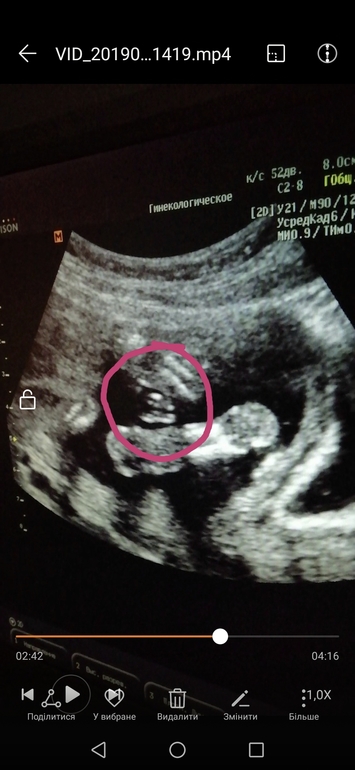

Но вот интересно, у кого ещё были фото с такого ракурса? Снизу?) тоже так торчал?)) второе фото) 14 неделя)

Если это половой бугорок, то да- это мальчик. У мальчиков и девочек одинаковые там на этом сроке, только у мальчиков торчит вверх, а у девочек вниз он смотрит или параллельно телу. К 16 неделями у девочек этот отросток уходит во внутрь и превращается в клитор ,ну а мальчика форммруется пенис ) Мне на 13 неделе сказали что мальчик и у нас торчал вверх . Врач прям показала и все обьяснила про бугорки )

Девочки не могу фото прикрепить ,кому не сложно зайдите в дневник посмотрите пожалуйста точно мальчики,а то и я что -то сомневаться стала ) просто ракурс у нас какой-то необычный прям ,фото сделали когда вагинально смотрели.